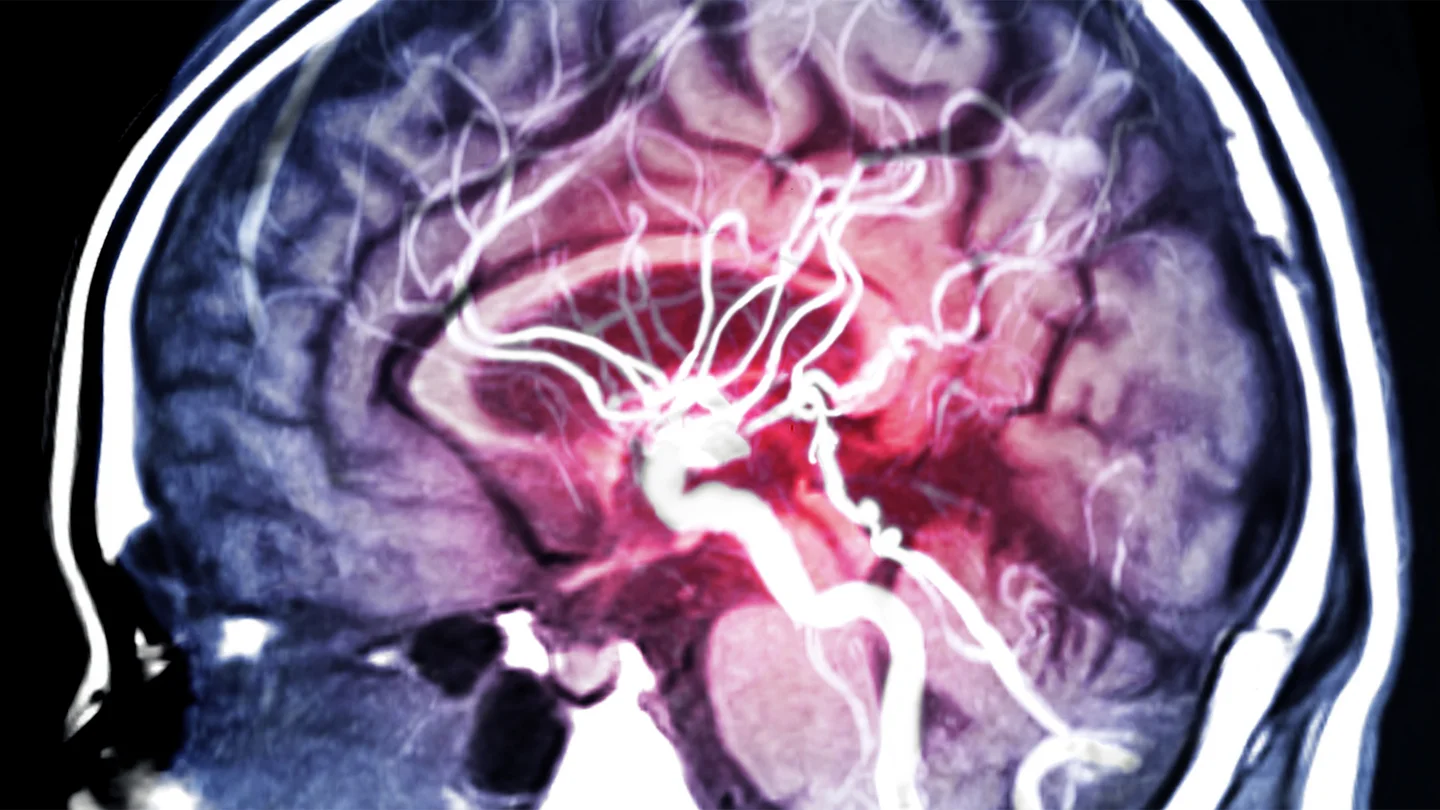

Menschliches Gehirn im Querschnitt: Blutgefäße und Hirnschlagader sind sichtbar. Menschliches Gehirn im Querschnitt: Blutgefäße und Hirnschlagader sind sichtbar.

Aneurysmen können an verschiedenen Arterien entstehen, beispielsweise an der Hauptschlagader im Bauch. Befindet sich die Wölbung an einer Schlagader des Gehirns, spricht man von einem Hirnaneurysma oder Hirnarterienaneurysma. Häufig bilden sich solche Aneurysmen an Verzweigungsstellen der Arterien, über die das Gehirn mit Blut versorgt wird. Wenn ein Hirnaneurysma reißt, kommt es zu einer lebensbedrohlichen Hirnblutung.

Mit einer digitalen Subtraktionsangiographie (DSA) lassen sich Aneurysmen besonders gut sichtbar machen: Dabei wird eine Röntgenaufnahme mit und eine Aufnahme ohne Kontrastmittel gemacht. Daraus kann der Computer anschließend ein Bild errechnen, auf dem nur noch die Blutgefäße zu sehen sind.